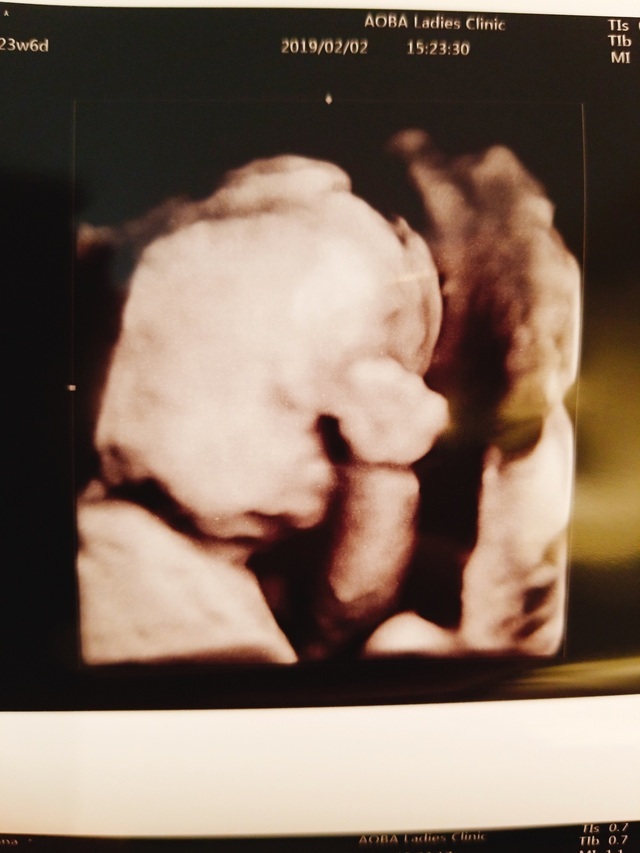

23週0日(23w0d・不明)|ともかりん さん(28歳)

エコー写真撮影時のエピソード:

やっとやっとお顔を見せてくれました。 このエコー写真だけまともなお顔。

先生も何回か挑戦してくれたけど、他は恥ずかしいのか背中やおててだけです。なのでこの1枚が唯一の宝物!恥ずかしいがりやは誰に似たのかな。